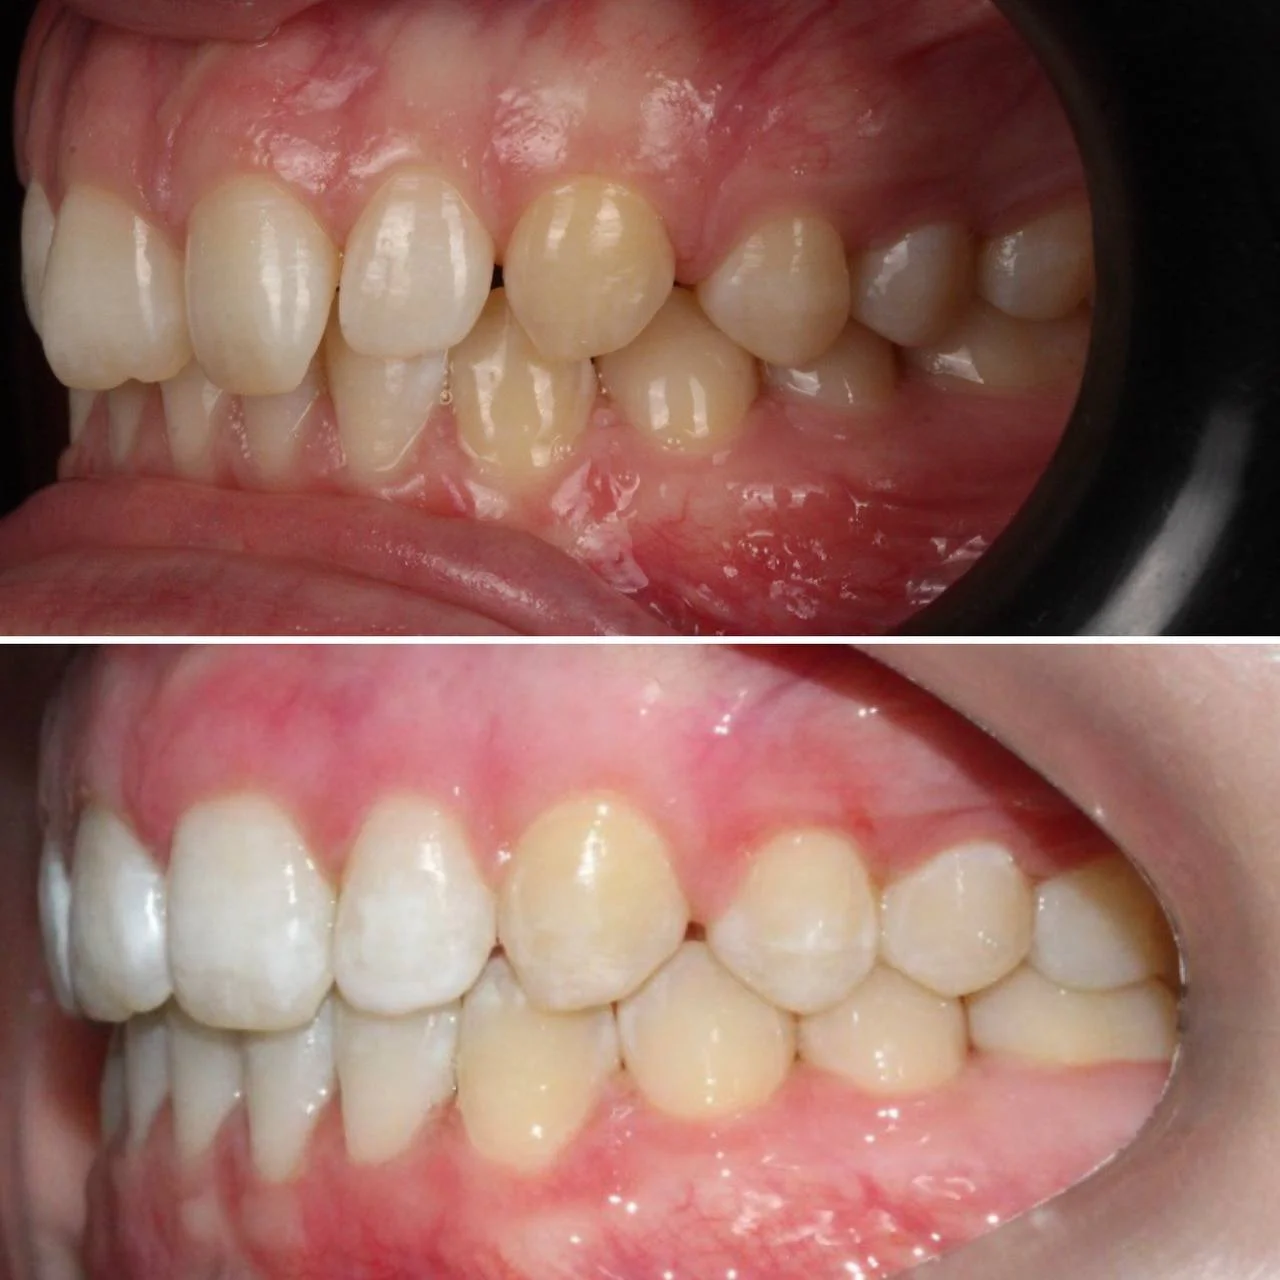

Скученность зубов, обе челюсти сужены — зубам не хватало места в ряду.

Брекет-система на обе челюсти. Расширить зубные дуги и убрать скученность. Срок — около 1,5 лет.

Проблема: Пациентка обратилась с одной жалобой — неровные зубы. При осмотре обнаружили, что обе челюсти сужены, зубам банально не хватает места, отсюда скученность. Зубы здоровые, ортопедия не нужна — чисто ортодонтический случай.

Решение: Установили брекеты на обе челюсти. Расширили дуги, убрали скученность — всё за 15 месяцев. Визиты раз в 4–6 недель для замены дуг. После снятия зафиксировали ретейнеры на обе челюсти, сняли сканы для кап. Ортопед подтвердил, что протезирование не требуется. Терапевт рекомендовал лечение — пациентка записана.